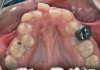

Fig 1. Functional shift in centric occlusion.

Figure 1

Fig 2. Functional shift in centric relation.

Figure 2

A common developmental abnormality is a localized anterior crossbite on permanent incisors, which may lead to trauma to these teeth. The most common cause of localized incisor crossbite is an anterior occlusal interference, which causes a functional shift when the patient moves from centric relation to centric occlusion (Figure 1 and Figure 2). This is not a true class III malocclusion, and proper diagnosis is critical to select the correct treatment. Sometimes this bite relationship is called a pseudo-class III relationship.2 Intervention in these cases is important because these teeth are at higher risk for recession, periodontal damage, and incisal chipping. Limited anterior braces and sometimes a palatal expander may be used to place the maxillary incisors facial to the mandibular incisors; this is referred to as "jumping the bite."